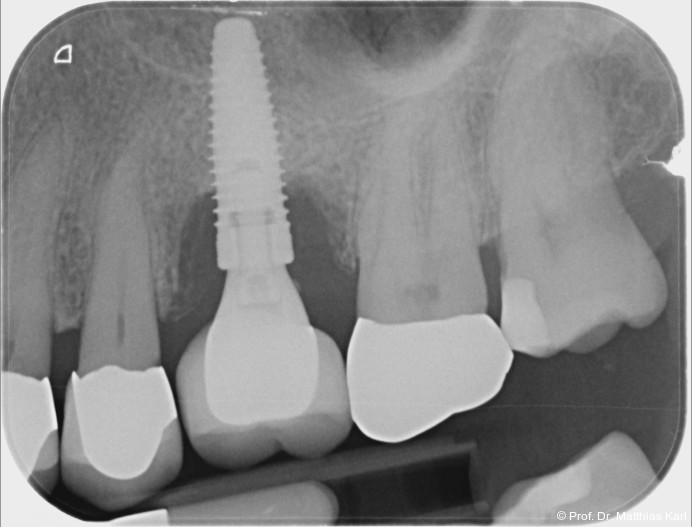

Mikrobewegungen im Verhältnis zum umgebenden Knochenlager. Die Vermeidung solcher Bewegungen ist essenziell, um eine erfolgreiche Osseointegration und damit die Entwicklung einer sekundären, biologisch bedingten Stabilität zu ermöglichen.18 Zur Verkürzung der Behandlungsdauer und zur Ermöglichung einer frühzeitigen prothetischen Versorgung wurden die klassischen operativen Protokolle angepasst. Hierzu zählen die untermaßige Implantatbettpräparation7 sowie der Einsatz konischer Implantatkörper21 (Abb. 1a–2b) mit ausgeprägt aggressiver Gewindegeometrie.8, 14 Beide Maßnahmen führen zu einer erhöhten Kompression des Alveolarknochens, insbesondere in den kortikalen Anteilen.11, 22

Zur Reduktion der Knochenkompression, insbesondere der bukkal gelegenen Lamelle (Abb. 3), werden derzeit Implantate mit dreieckigem Querschnitt10, 12 sowie Implantate mit zervikal reduziertem Durchmesser16 angeboten. Diese scheinen jedoch im Gegensatz zur subkrestalen Positionierung (Abb. 4a–c) von Implantaten23 keine signifikanten Vorteile zu bieten. Bohrprotokolle, welche sowohl auf das jeweilige Implantatsystem als auch auf die vorliegende Knochenqualität abgestimmt sind, haben ebenfalls das Ziel, zu hohe Einbringdrehmomente zu vermeiden.